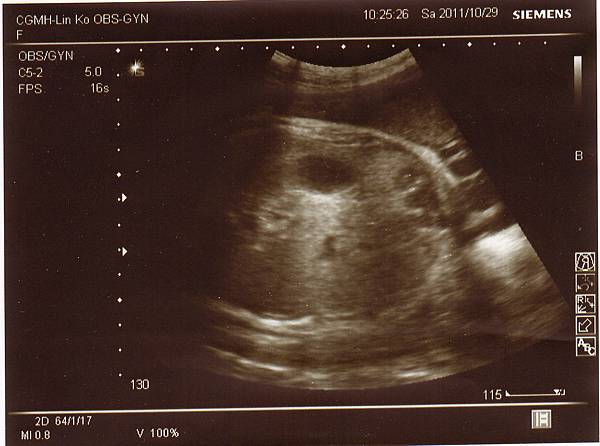

希望她可以到11月再出生,今天除了例行性產檢外,

還到三樓產房做胎心音監測,

1029-2.jpg